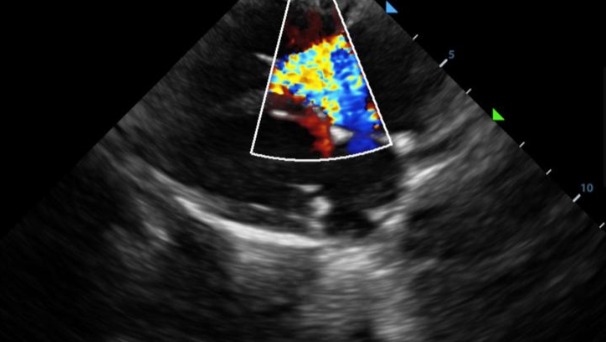

Hola, mi cachorro Pakito sufre de una mal formación en el corazón, tiene displasia en la válvula tricúspide. Explicándolo mal resumido sus válvulas no funcionan adecuadamente y no expulsa la sangre del corazón como debería por lo que el corazón agranda y agranda hasta que colapsa.